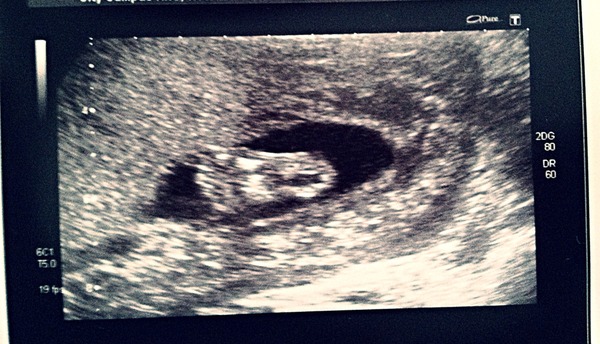

nickyjlees · 20/07/2014 21:44

Ps my son's teeny tiny little foot! Our lovely sonographer gave this to us as a free extra pic with our 3 lovely images of his lovely little face :)

Dec 2014 Thread #5 - Battered and bruised we limp through the second trimester